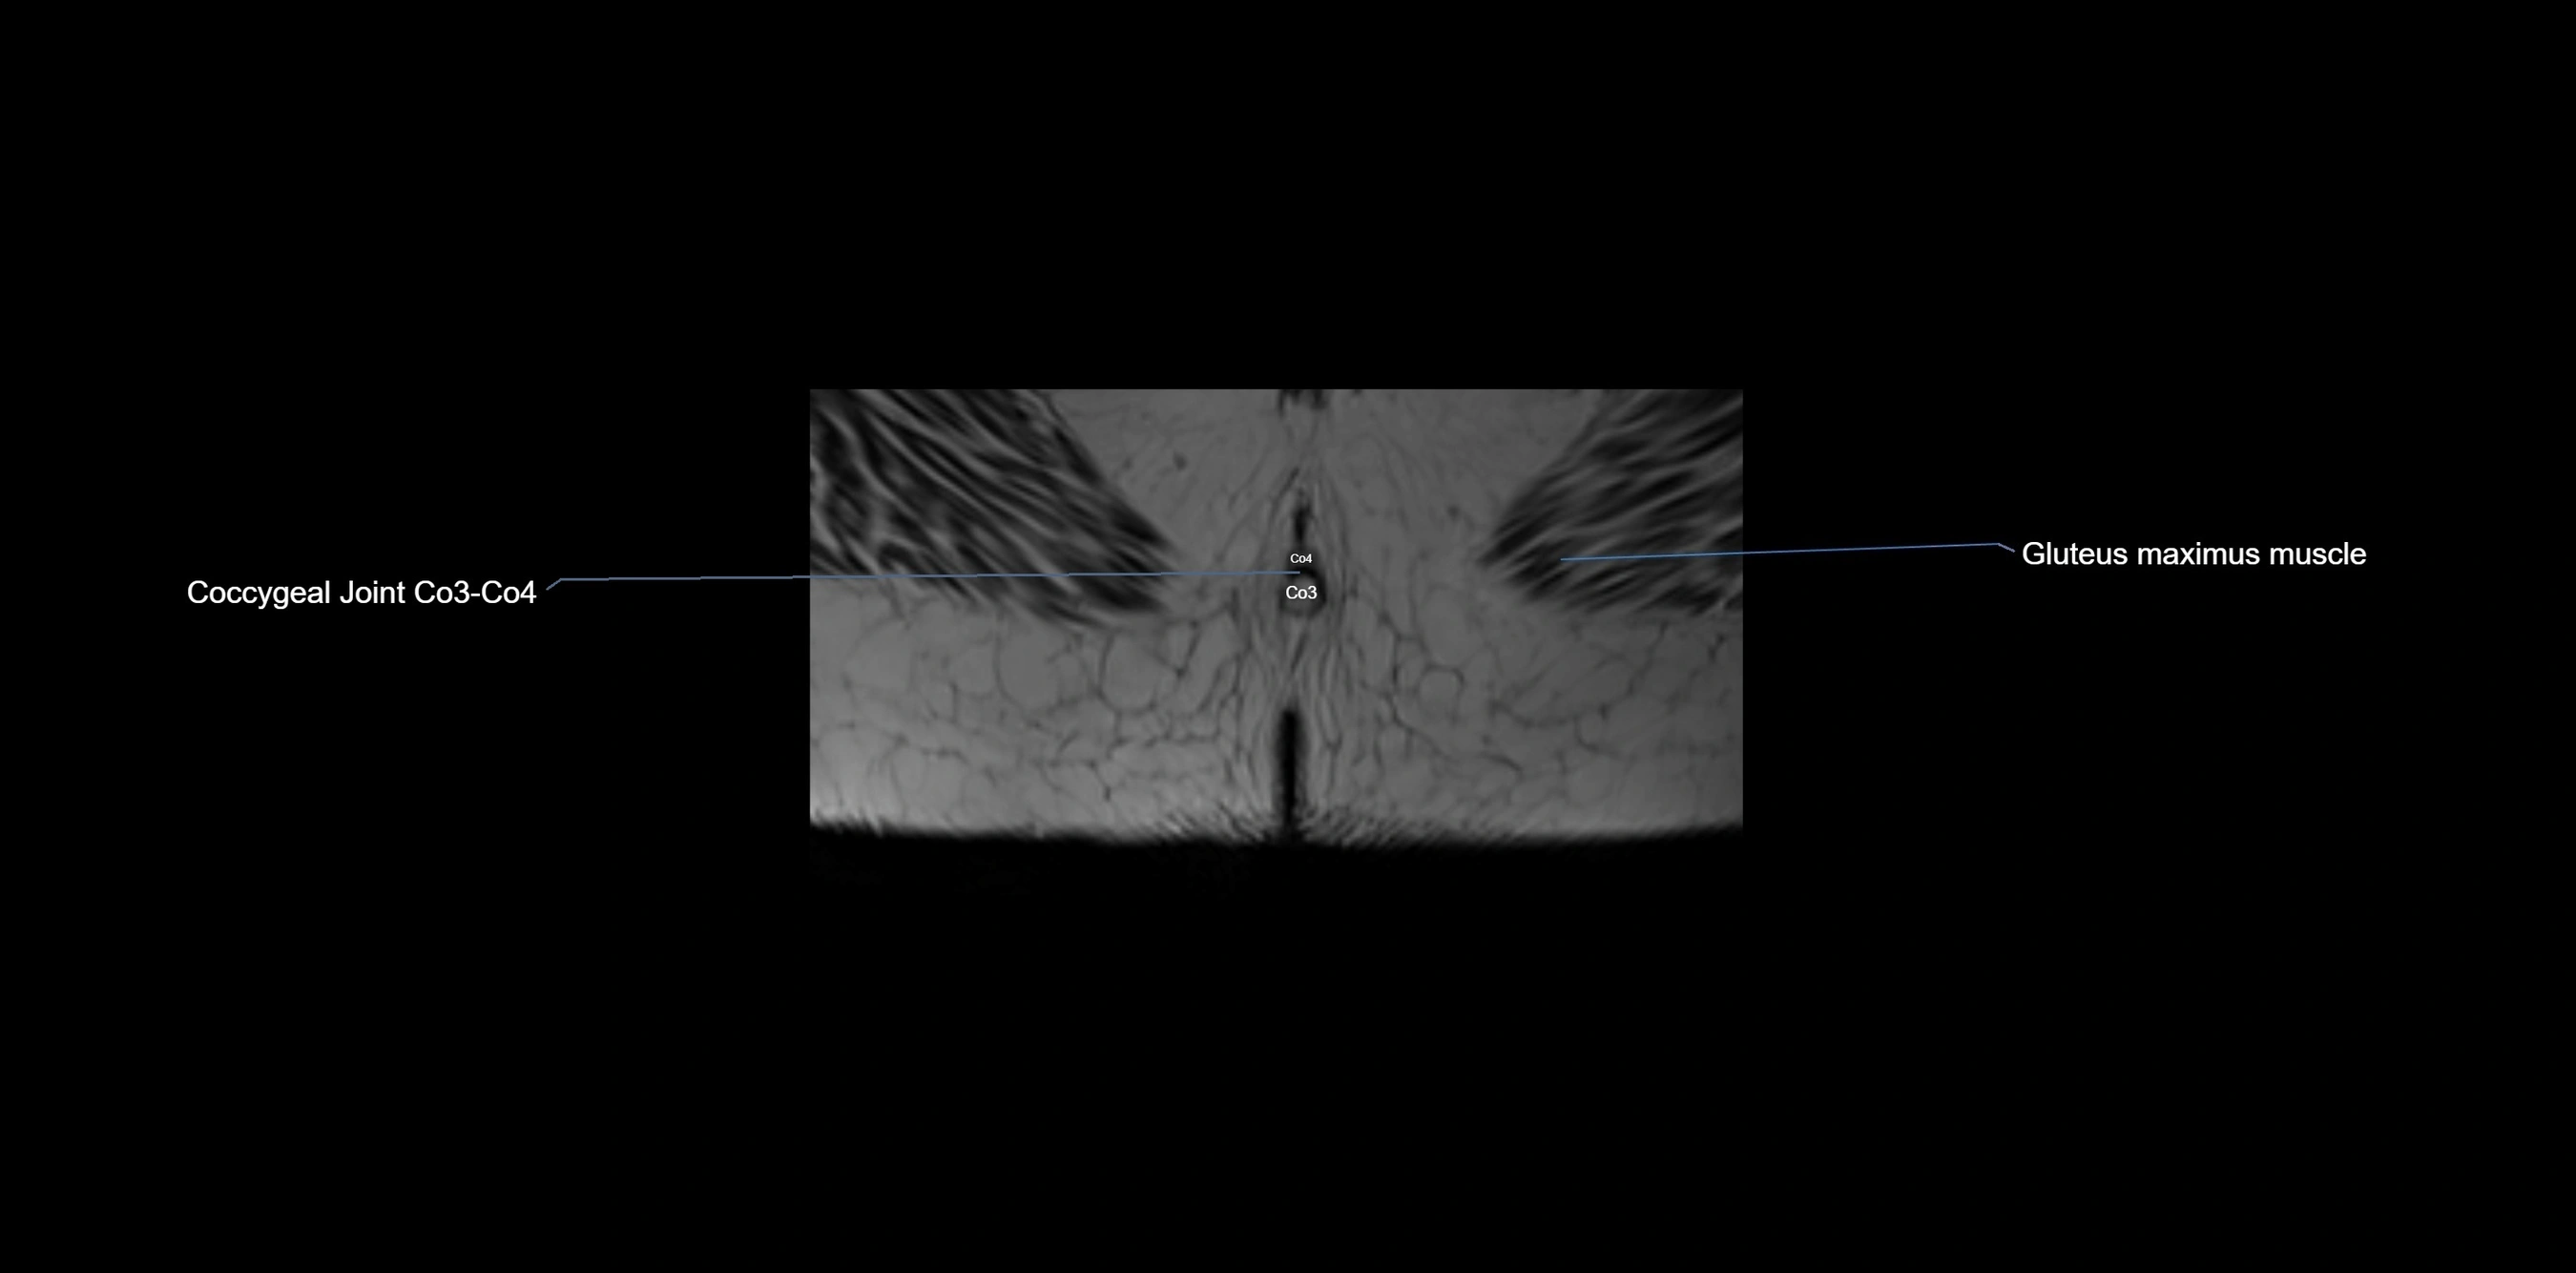

MRI image

image